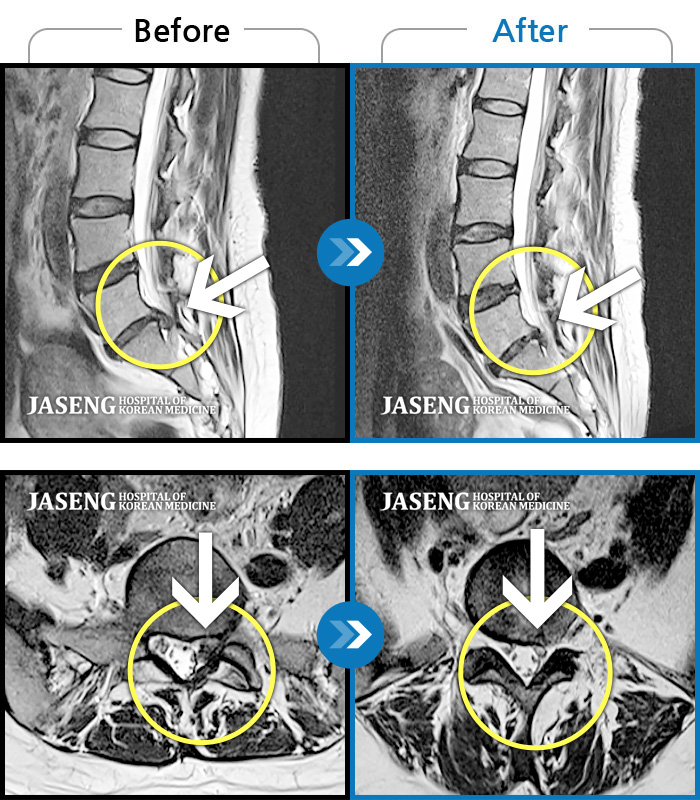

MRI 치료사례

허리 통증과 왼쪽 골반에서 종아리까지 당기는 통증